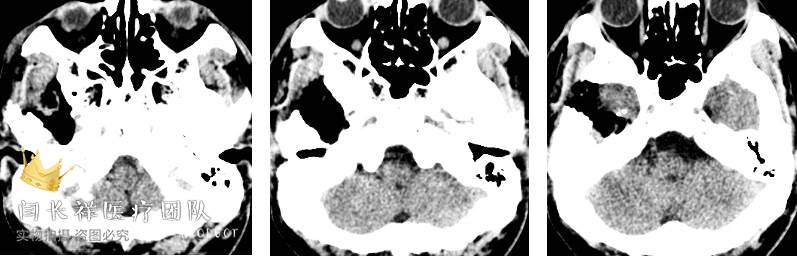

术后6小时复查头部CT示肿瘤切除满意。

中颅窝-颞下窝占位

术后头部增强MRI示肿瘤切除满意。

术后恢复顺利,术前症状显著改善。